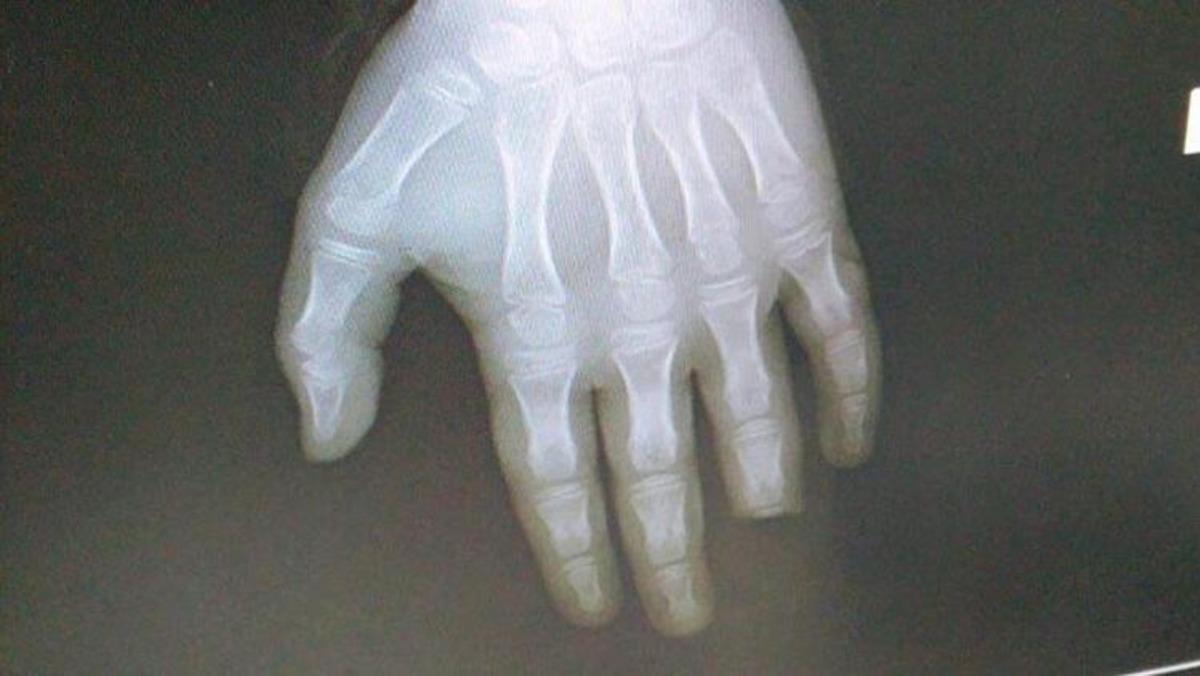

Mersin'in Anamur ilçesinde denize giren 8 yaşındaki E.B.D. balon balığının saldırısı sonucu sol el yüzük parmağının yarısını kaybetti.

SOL EL YÜZÜK PARMAĞININ YARISI KOPTU

E.B.D. ambulansla Anamur Devlet Hastanesine kaldırıldı. Burada yapılan ilk tedavinin ardından Antalya Devlet Hastanesine kaldırılan E.B.D.’nin sol el yüzük parmağının yarısının koptuğu belirlendi.